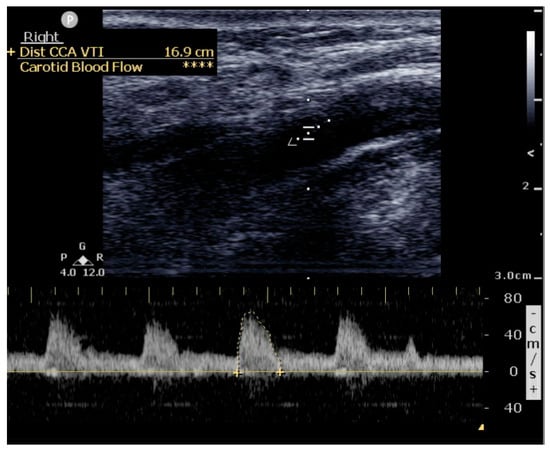

- CCA PWD VTI—Common Carotid Artery Pulsed Wave Doppler Time Velocity Integral.

- Increase in carotid blood flow by 10% after a fluid challenge. (Passive leg raise).